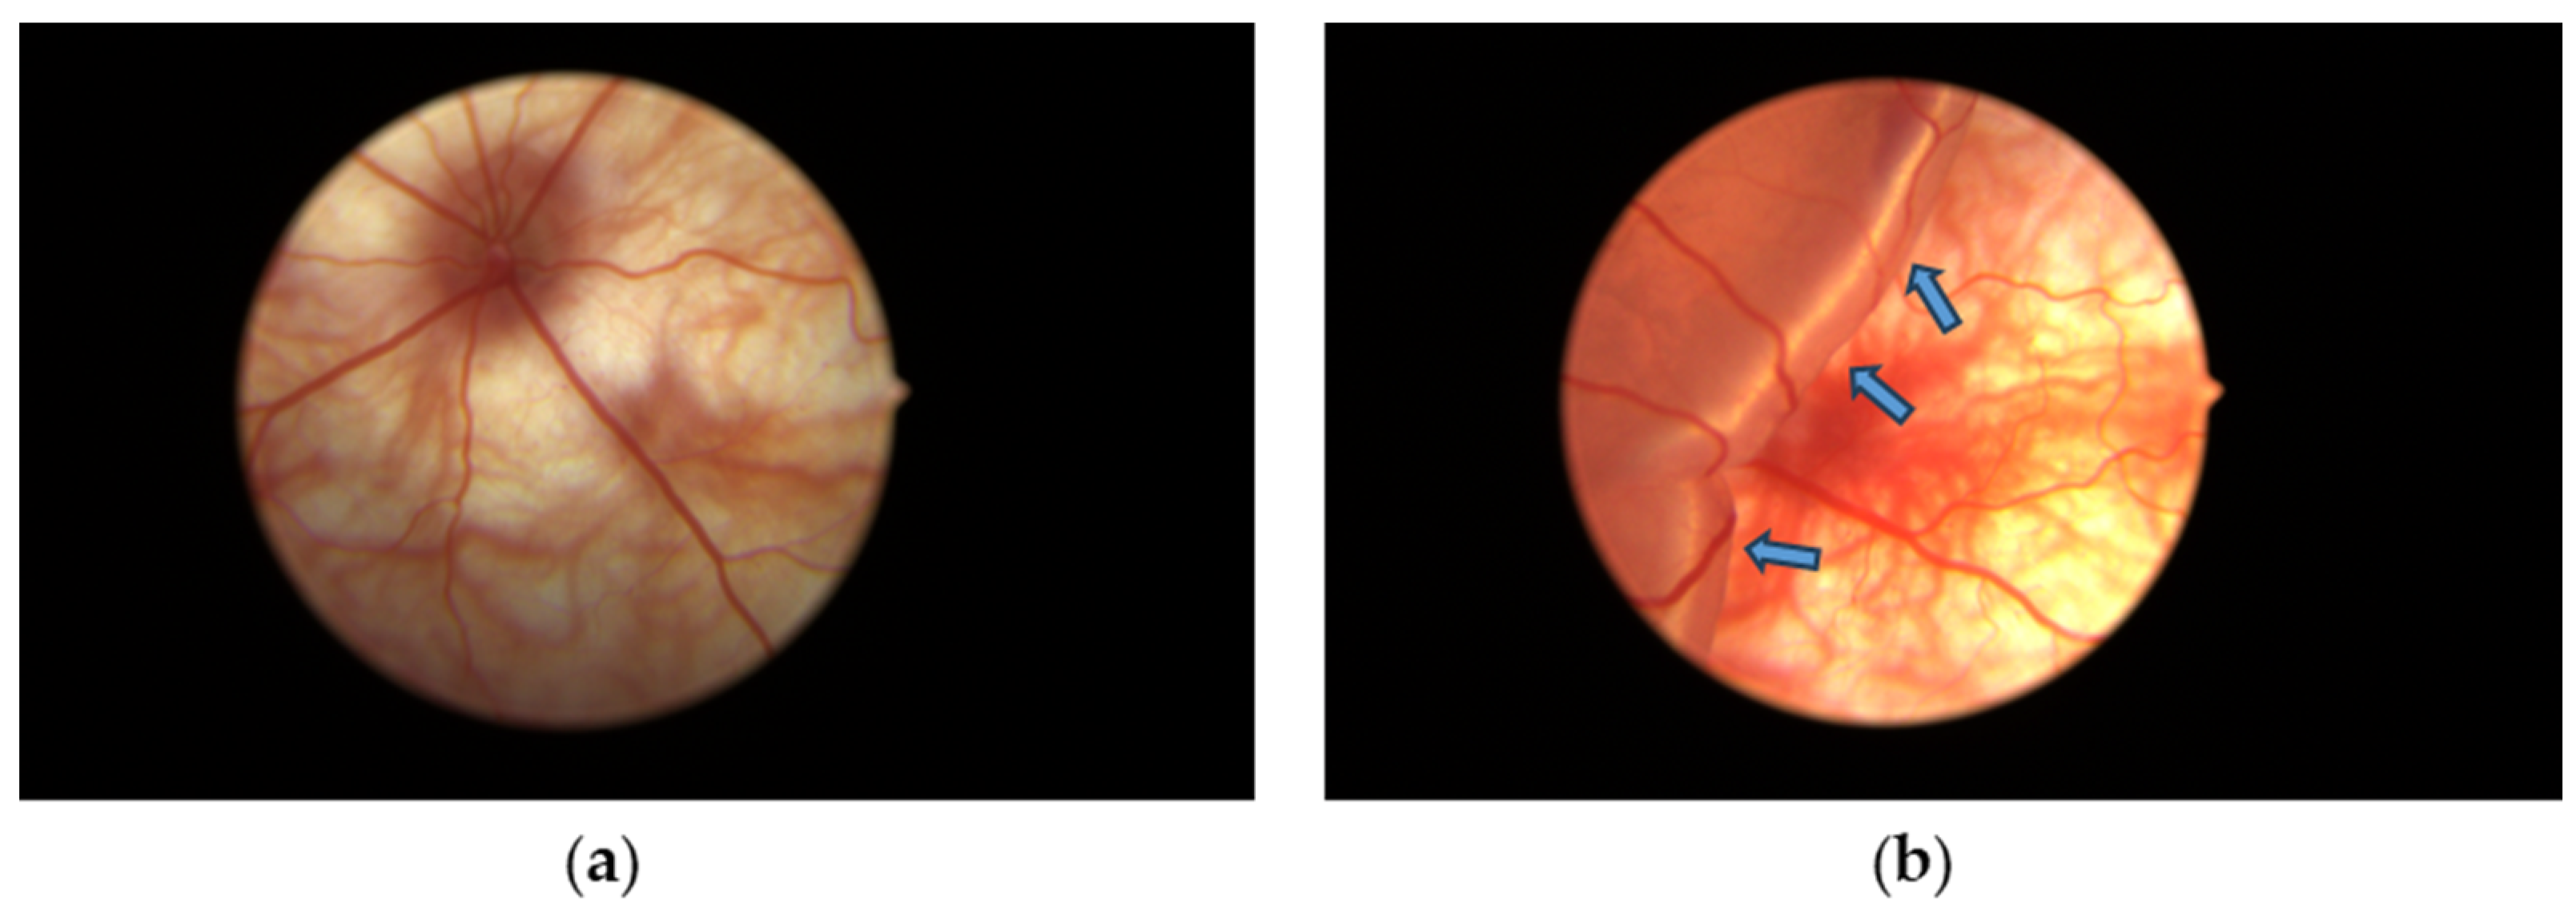

3.1. Retinal Detachment Features